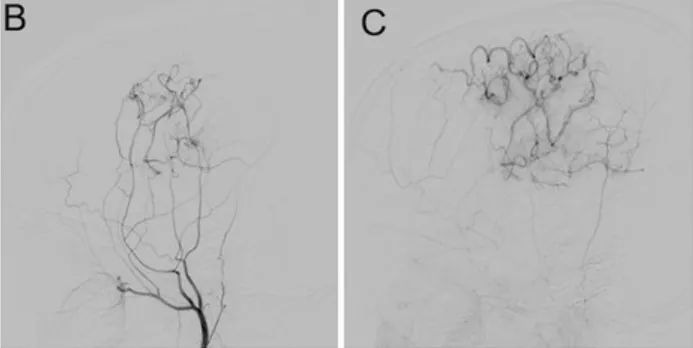

术后6个月复查显示桥血管通畅,小智偏瘫症状完全消失,恢复学习和活动能力。

术后6个月随访DSA显示旁路血管通畅,左大脑中动脉供血区血流显著改善(图B、图C)。